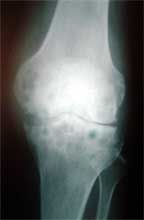

膝关节类风湿关节炎,胫骨近端骨缺损,成蜂窝状    MRI显示骨破坏程度